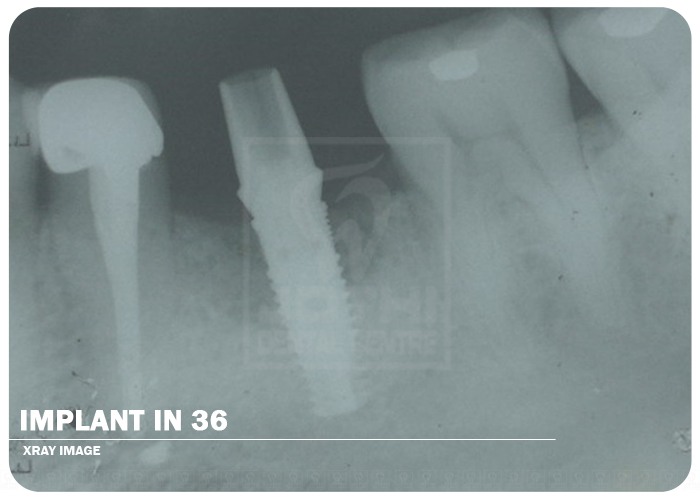

Implant In 36